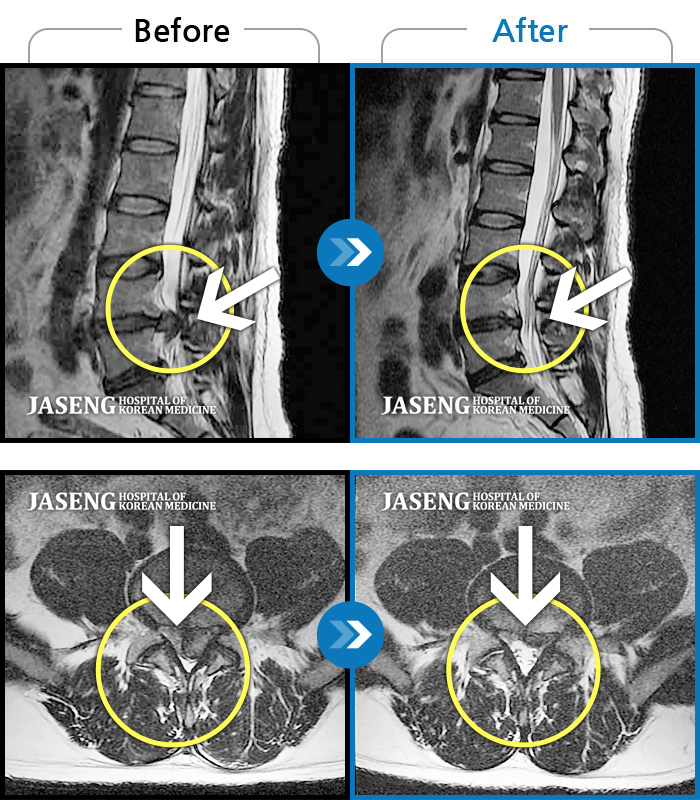

Before

After

환자에게 사전 동의를 받아 동일 조건에서 촬영되었습니다.

개인에 따라 치료 후 부작용이 발생할 수 있으니 의료진과 상담 후 치료를 진행하시기 바랍니다.

하부 요추, 골반 양측 통증, 좌측 다리 당김 및 통증

심한 허리 통증과 우측 다리 통증